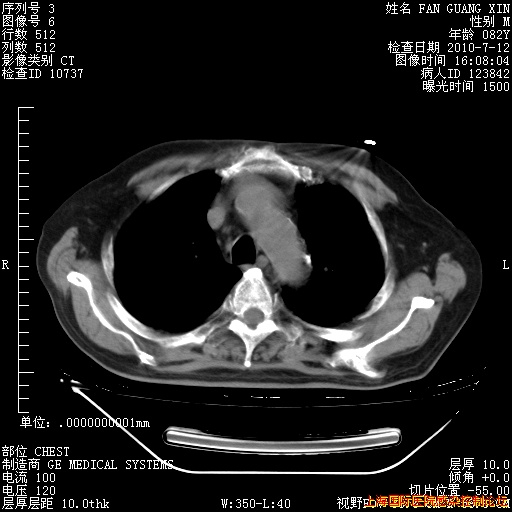

今天复查CT

今天CT

整整相隔30天的肺部CT好像有所好转啊。甲强龙减量第3天,需要观察体温。